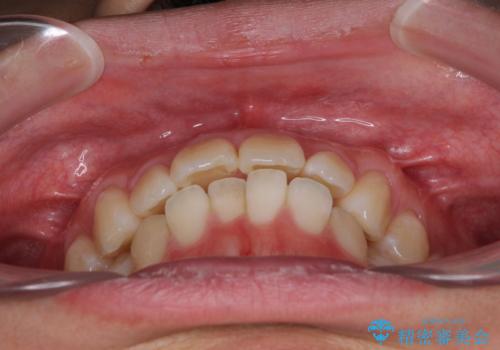

少しでも口元を閉じやすく インビザラインによる前突の解消

- 全体的なデコボコと、前歯の前に出ている感じを気にして来院された患者様です。

患者様と相談の上、非抜歯にてインビザラインを用いて矯正治療を行うこととし、IPR(歯と歯の間)並びに歯列全体の後方移動により口元の突出感の改善することとしました。